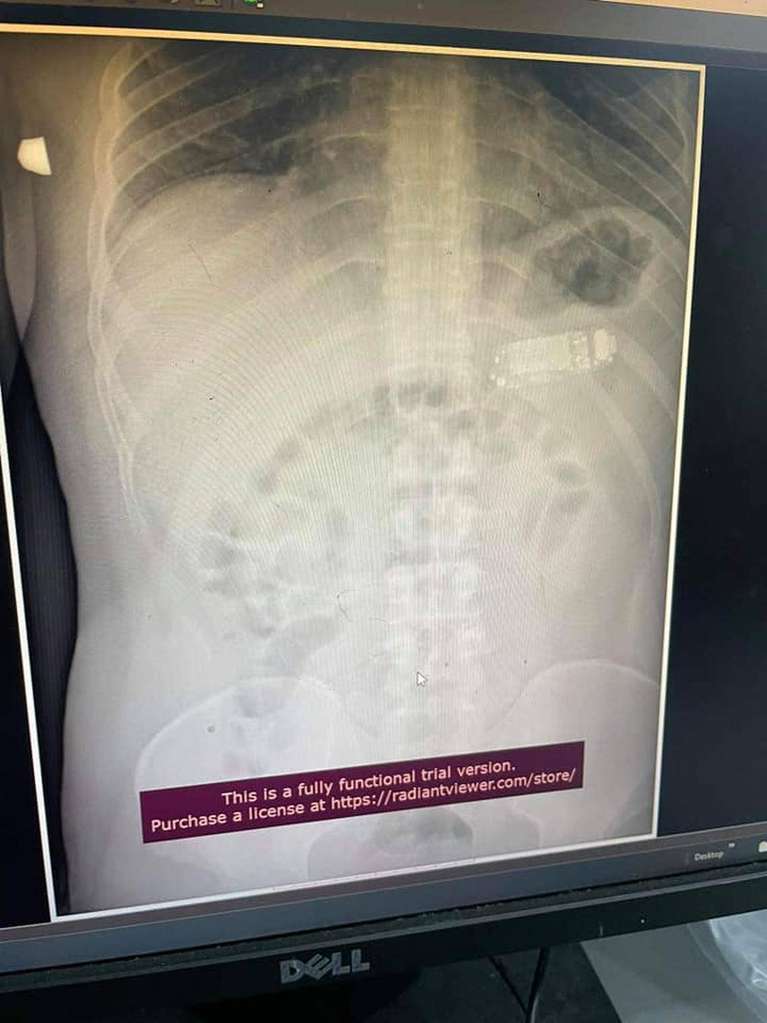

Một tù nhân ở Nga đã khiến bác sĩ kinh ngạc khi nuốt trọn chiếc điện thoại vào bụng. Người này đã bị đau bụng trong nhiều ngày và cơn đau không hề giảm đi. Khi được thăm khám, các bác sĩ đã thực hiện phẫu thuật để lấy chiếc điện thoại ra ngoài.

Một tù nhân 33 tuổi ở Kosovo đã phàn nàn về những cơn đau dạ dày trong suốt nhiều ngày. Sau khi được đưa tới một phòng khám ở thủ đô Pristina, các bác sĩ đã tá hoả khi phát hiện ra trong dạ dày của người đàn ông này là một chiếc... điện thoại Nokia 3310.

Bác sĩ Skender Telaku cùng nhóm cộng sự đã tiến hành một ca phẫu thuật nội soi để lấy chiếc điện thoại ra. Sau hai giờ, ca phẫu thuật đã thành công.

"Bằng phương pháp nội soi, không cần mở dạ dày, chúng tôi đã lấy thành công chiếc điện thoại bị tách ra làm ba phần. Nó giống như đi bộ qua một bãi mìn vậy, nhưng mọi thứ đã diễn ra tốt đẹp", bác sĩ Skender Telaku nói.

Bác sĩ này nhận định phần nguy hiểm nhất của điện thoại là pin. Những thành phần độc hại bên trong pin, cụ thể là axit ăn mòn, có thể gây ảnh hưởng tới các cơ quan nội tạng. May mắn thay, pin và các thành phần còn lại của chiếc điện thoại đã được lấy ra một cách an toàn mà không để lại bất kỳ biến chứng nào.

Ảnh chụp X-quang của tù nhân Kosovo

Tù nhân 33 tuổi nói với các bác sĩ rằng anh ta đã nuốt chiếc Nokia 3310 4 ngày trước khi đến phòng cấp cứu. Anh này bị nghi ngờ đã sử dụng điện thoại để liên lạc với những người bên ngoài trại giam. Chưa rõ bằng cách nào mà người này có thể nuốt được cả một chiếc điện thoại, nhưng rất có thể đây là một nỗ lực tuyệt vọng nhằm che giấu nó khỏi con mắt của các quản ngục.